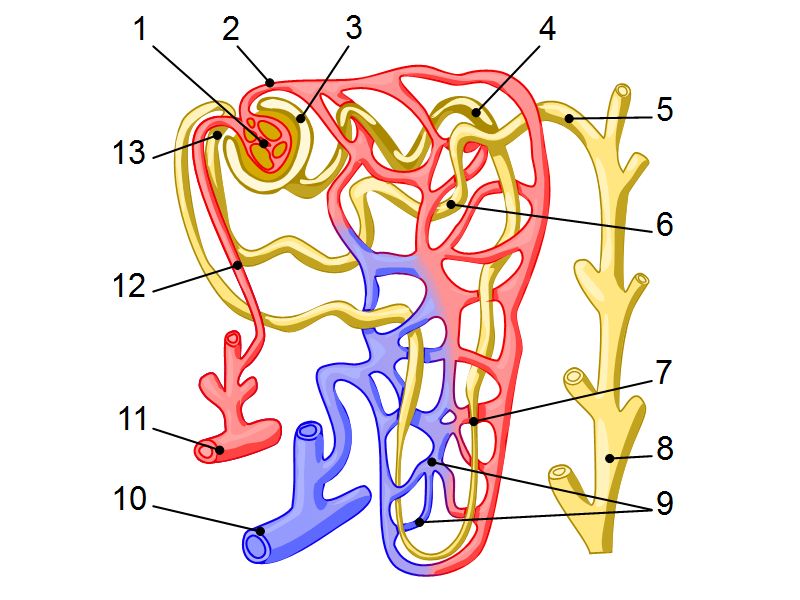

Nephron

- Unit responsible for

- Filtration

- Excretion

- Resorption

- Include

- Kidney tubule

- Glomerulus

- Exclude

- Collecting tubule

Nephron

- Renal corpuscle

- Proximal convoluted segment

- Long loop of Henle

- Descending portion

- Ascending portion

- Distal convoluted segment

Blood flow

- Efferent arteriole

- Smooth muscle in media

- Capillaries

- Fenestrated

- Afferent arteriole

- Smooth muscle in media

Juxtaglomerular complex

Area where distal convoluted tubule return to glomerulus and pass through the notch between the afferent and efferent arterioles. Modification of the wall of the tubule and afferent arteriole and presence of specialised cells in the connective tissue.Modifications

- Distal convoluted tubule

- Macula densa

- Narrow epithelial cells

- Nuclei densely packed

- CT cells

- Laci cells

- Similar to mesangial cells

- Afferent arteriole

- Modified smooth muscle cells

- Juxtaglomerular cells

- Secretory function